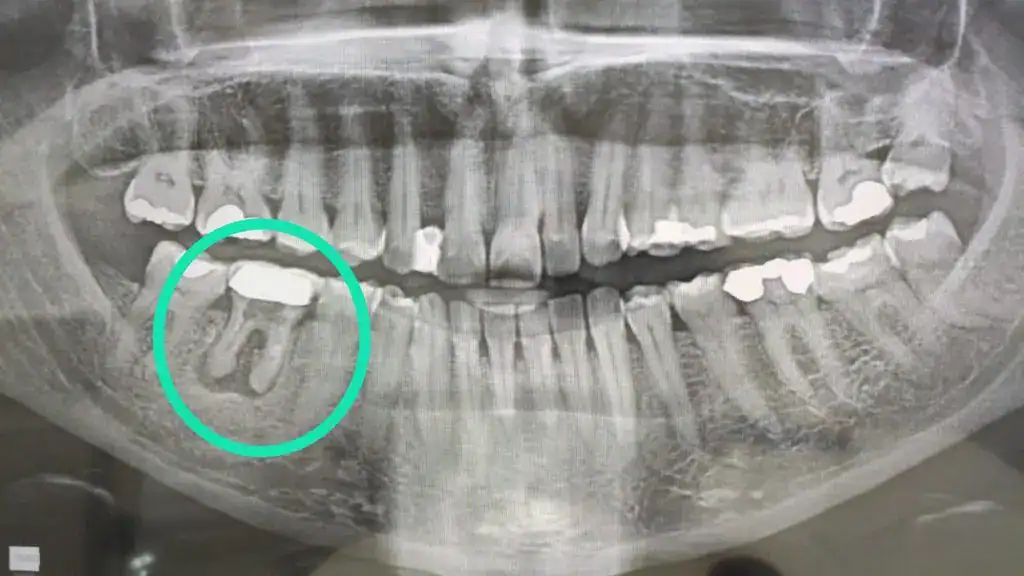

Un absceso dental es una acumulación de pus causada por una infección bacteriana en el diente o las encías. Aunque al inicio puede parecer solo una inflamación o dolor leve, si no se trata a tiempo, puede generar complicaciones serias que incluso se extienden al rostro o al cuello.

Para entender cómo debe tratarse correctamente un absceso, la odontóloga guatemalteca Dra. Mariana López, especialista en endodoncia, explica que “el tratamiento depende de la gravedad del absceso y de si el diente afectado puede salvarse o no”.

“El absceso puede causar dolor intenso, fiebre, mal aliento, encías inflamadas y enrojecidas, y en algunos casos, una bolita de pus visible en la encía”, detalla la Dra. López. En estos casos, lo más importante es no automedicarse y acudir al odontólogo inmediatamente.